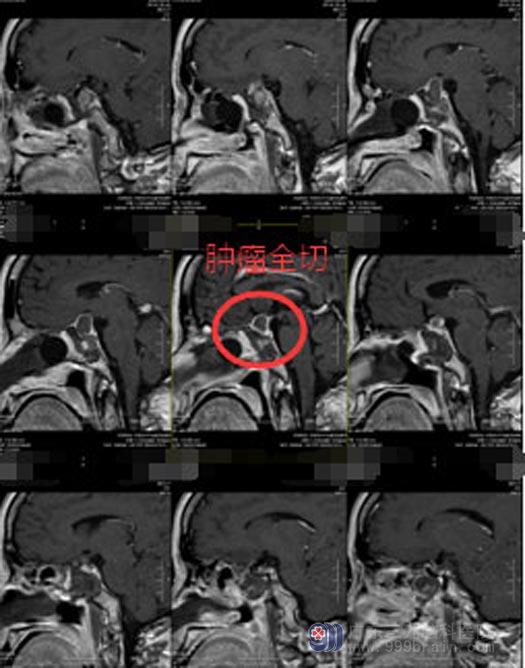

征得赖女士及其家人同意后,医院副院长、神经外五科主任鲁明带领团队为患者行“内镜经鼻蝶鞍区复发侵袭垂体腺瘤切除术+颅底重建术”,手术过程顺利。

术后,赖女士神清,无发热,无尿崩,左眼视物较术前清晰,垂体催乳素从术前的94.22ug/L降至40.44 ug/L。经过精心的治疗和护理,赖女士已满意出院。